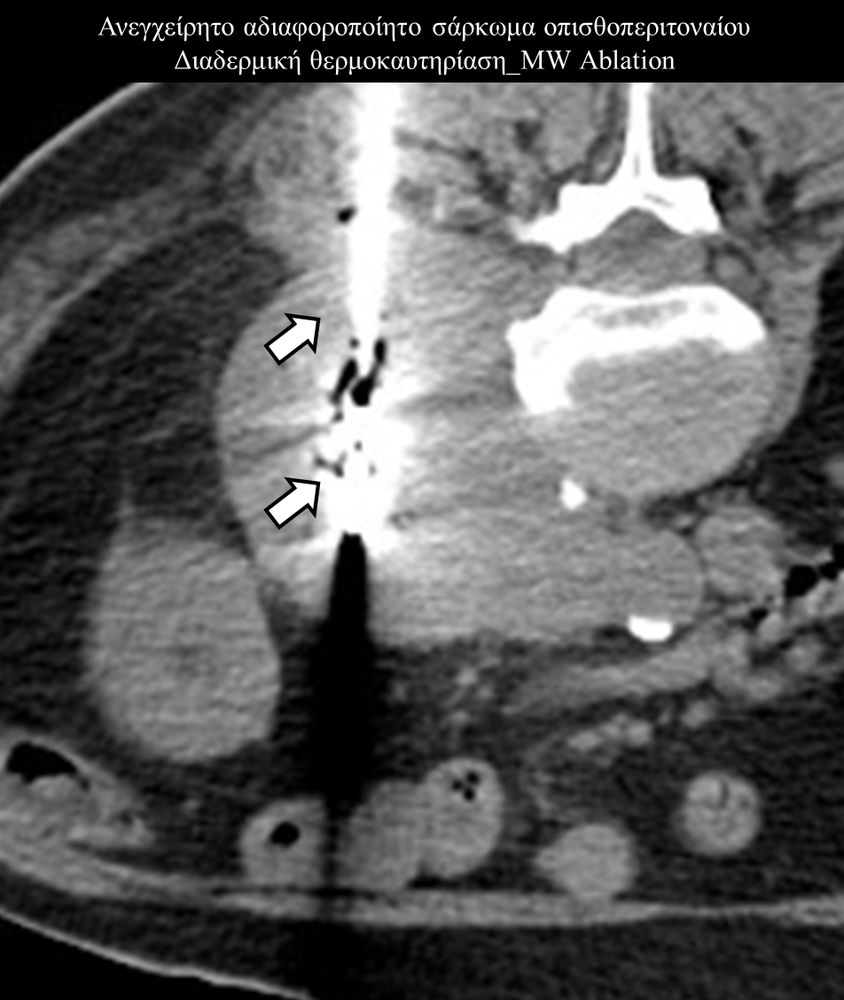

Πρόκειται για την πιο σύγχρονη τοπική θεραπεία όγκων του ήπατος, του νεφρού, του πνεύμονα, των οστών και των όγκων μαλακών μορίων. Παθοφυσιολογικά βασίζεται στην τοπική καταστροφή των καρκινικών κυττάρων με τη δημιουργία ιδιαίτερα υψηλών θερμοκρασιών εντός του όγκου. Αυτό επιτυγχάνεται με τοποθέτηση ειδικών ηλεκτροδίων εντός του όγκου υπό ακτινολογική καθοδήγηση (αξονικός τομογράφος ή υπέρηχος). Τα ηλεκτρόδια αυτά παράγουν υψηλή θερμοκρασία είτε με τη βοήθεια ραδιοσυχνοτήτων (RFablation), είτε με τη βοήθεια μικροκυμάτων (MWablation) και προκαλούν πηκτική νέκρωση των καρκινικών κυττάρων χωρίς να επηρεάζουν τα φυσιολογικά κύτταρα.Το αποτέλεσμα είναι μόνιμο.